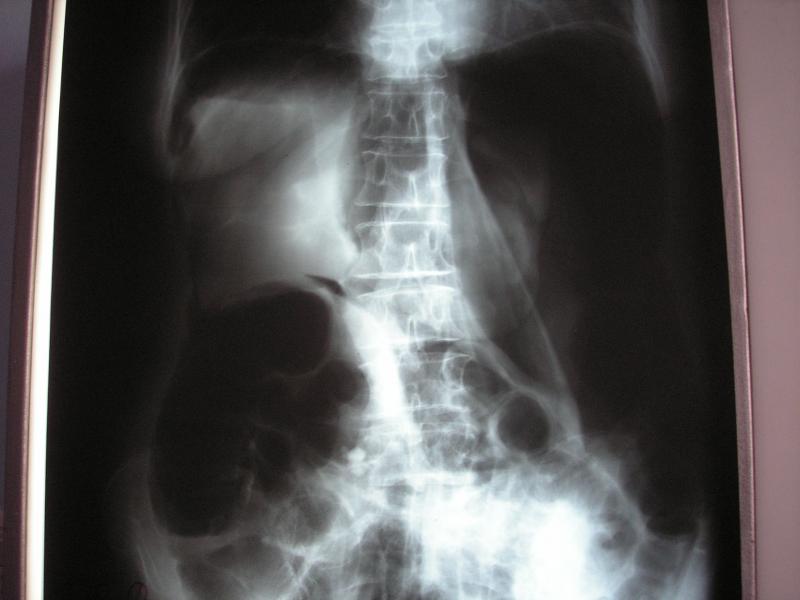

Isquemia mesentérica: Aguda y crónica